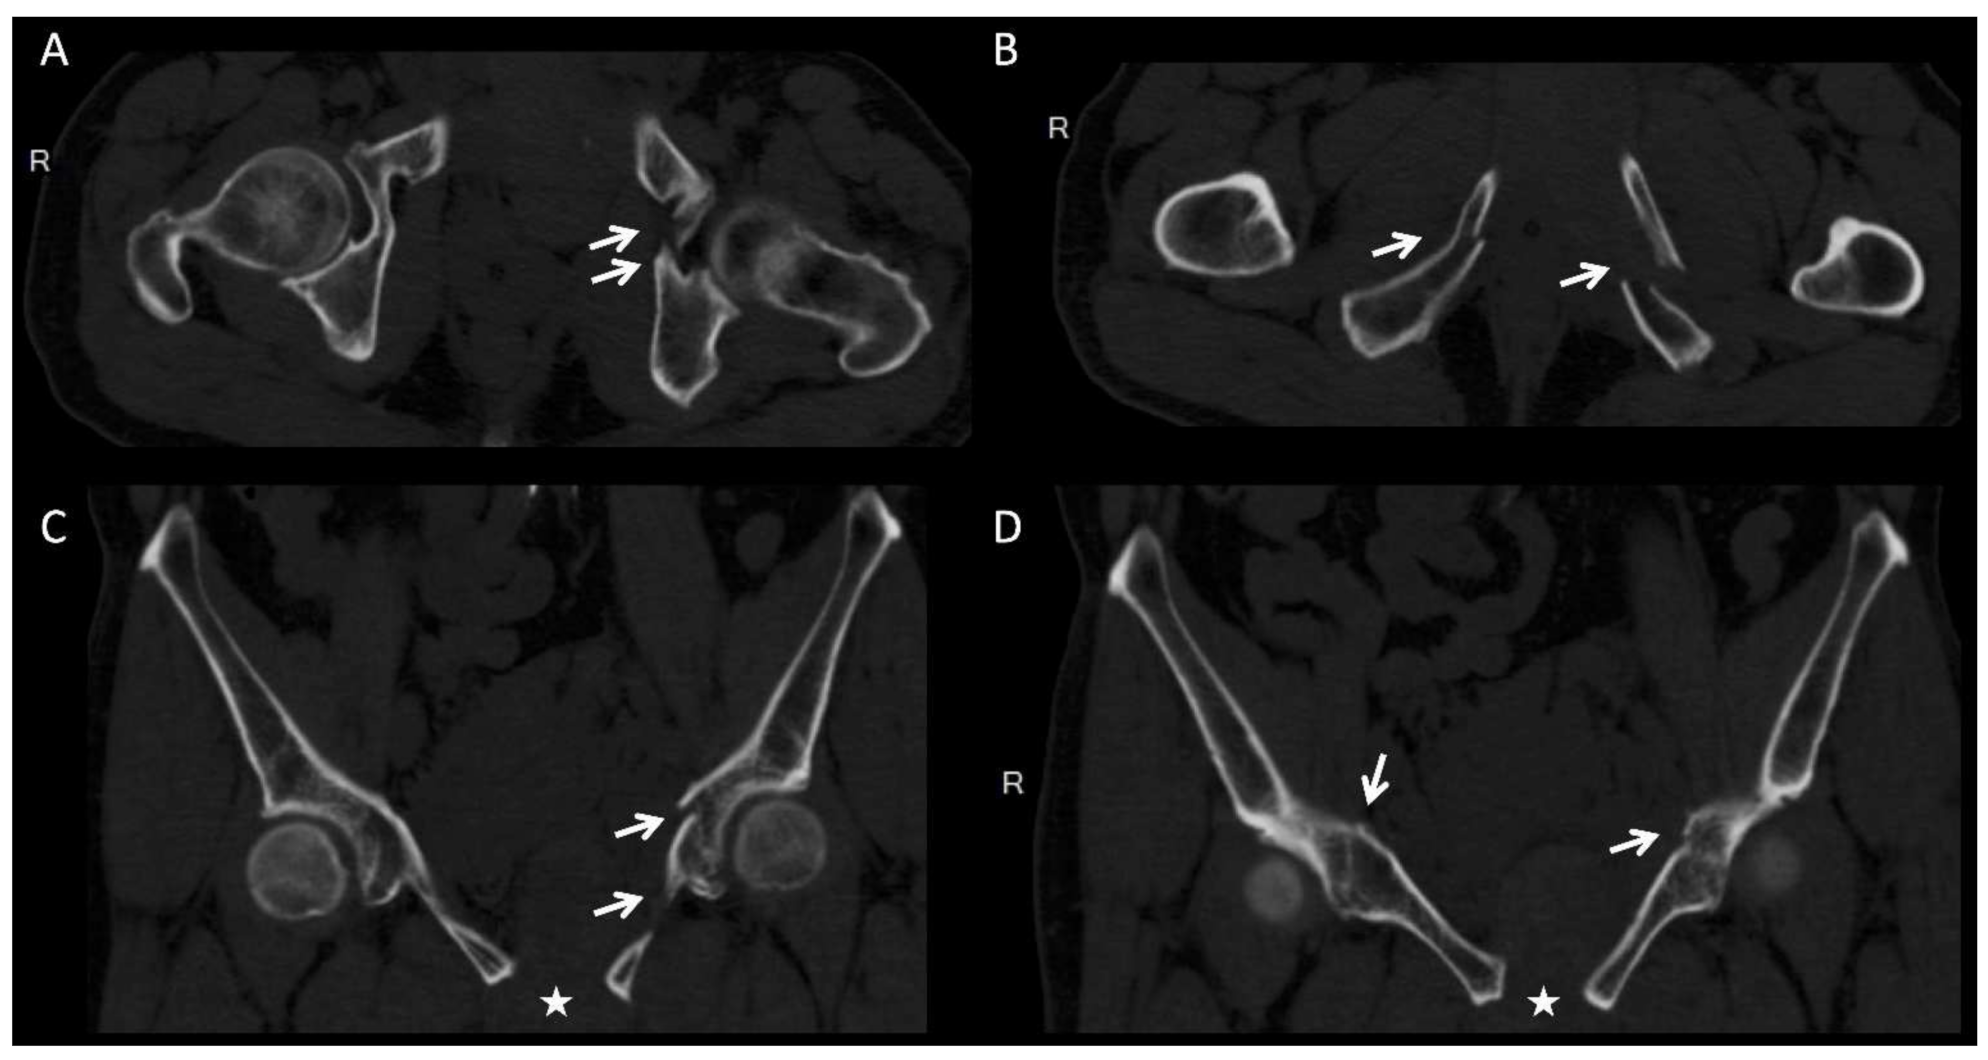

- Hsu, C.L.; Chou, Y.C.; Li, Y.T.; Chen, J.E.; Hung, C.C.; Wu, C.C.; Shen, H.C.; Yeh, T.T. Pre-operative virtual simulation and three-dimensional printing techniques for the surgical management of acetabular fractures. Int. Orthop. 2019, 43, 1969–1976. [Google Scholar] [CrossRef]